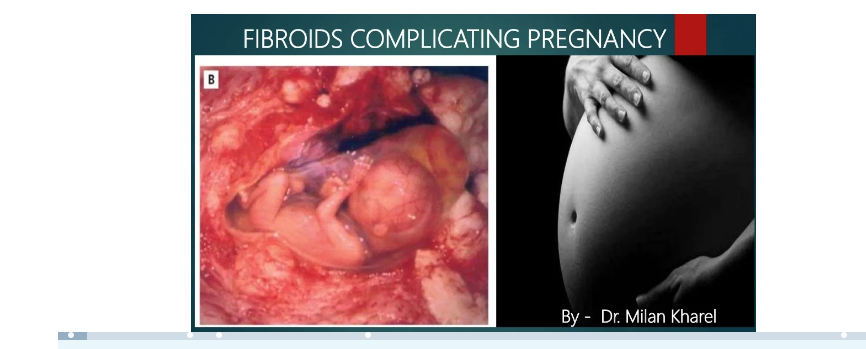

Infertility occurs primarily from the combination of fibroids, ovarian cysts, tubal blockage, and sometimes a hot stomach.

If, by chance, they get in, they’ll struggle with fibroids to gain space to grow.

But one common problem with the above is that 90% of the time, the fibroid grows back and stops you from getting pregnant and having your own baby.

For some, a fibroid can even grow to term, and they deliver it.